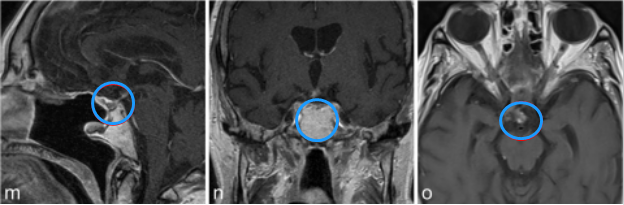

a–c图中,MR成像显示鞍上部分实性,部分囊性对比增强病变,高度可疑的颅咽管瘤。

j-l图表示,在3个月后复查MR检查,显示术后垂体柄处有肿瘤少量残留。

m-o图显示,磁共振成像分期立体定向放射治疗后22个月,显示肿瘤明显缩小。病人经氢化可的松和甲状腺激素的替代治疗恢复良好。